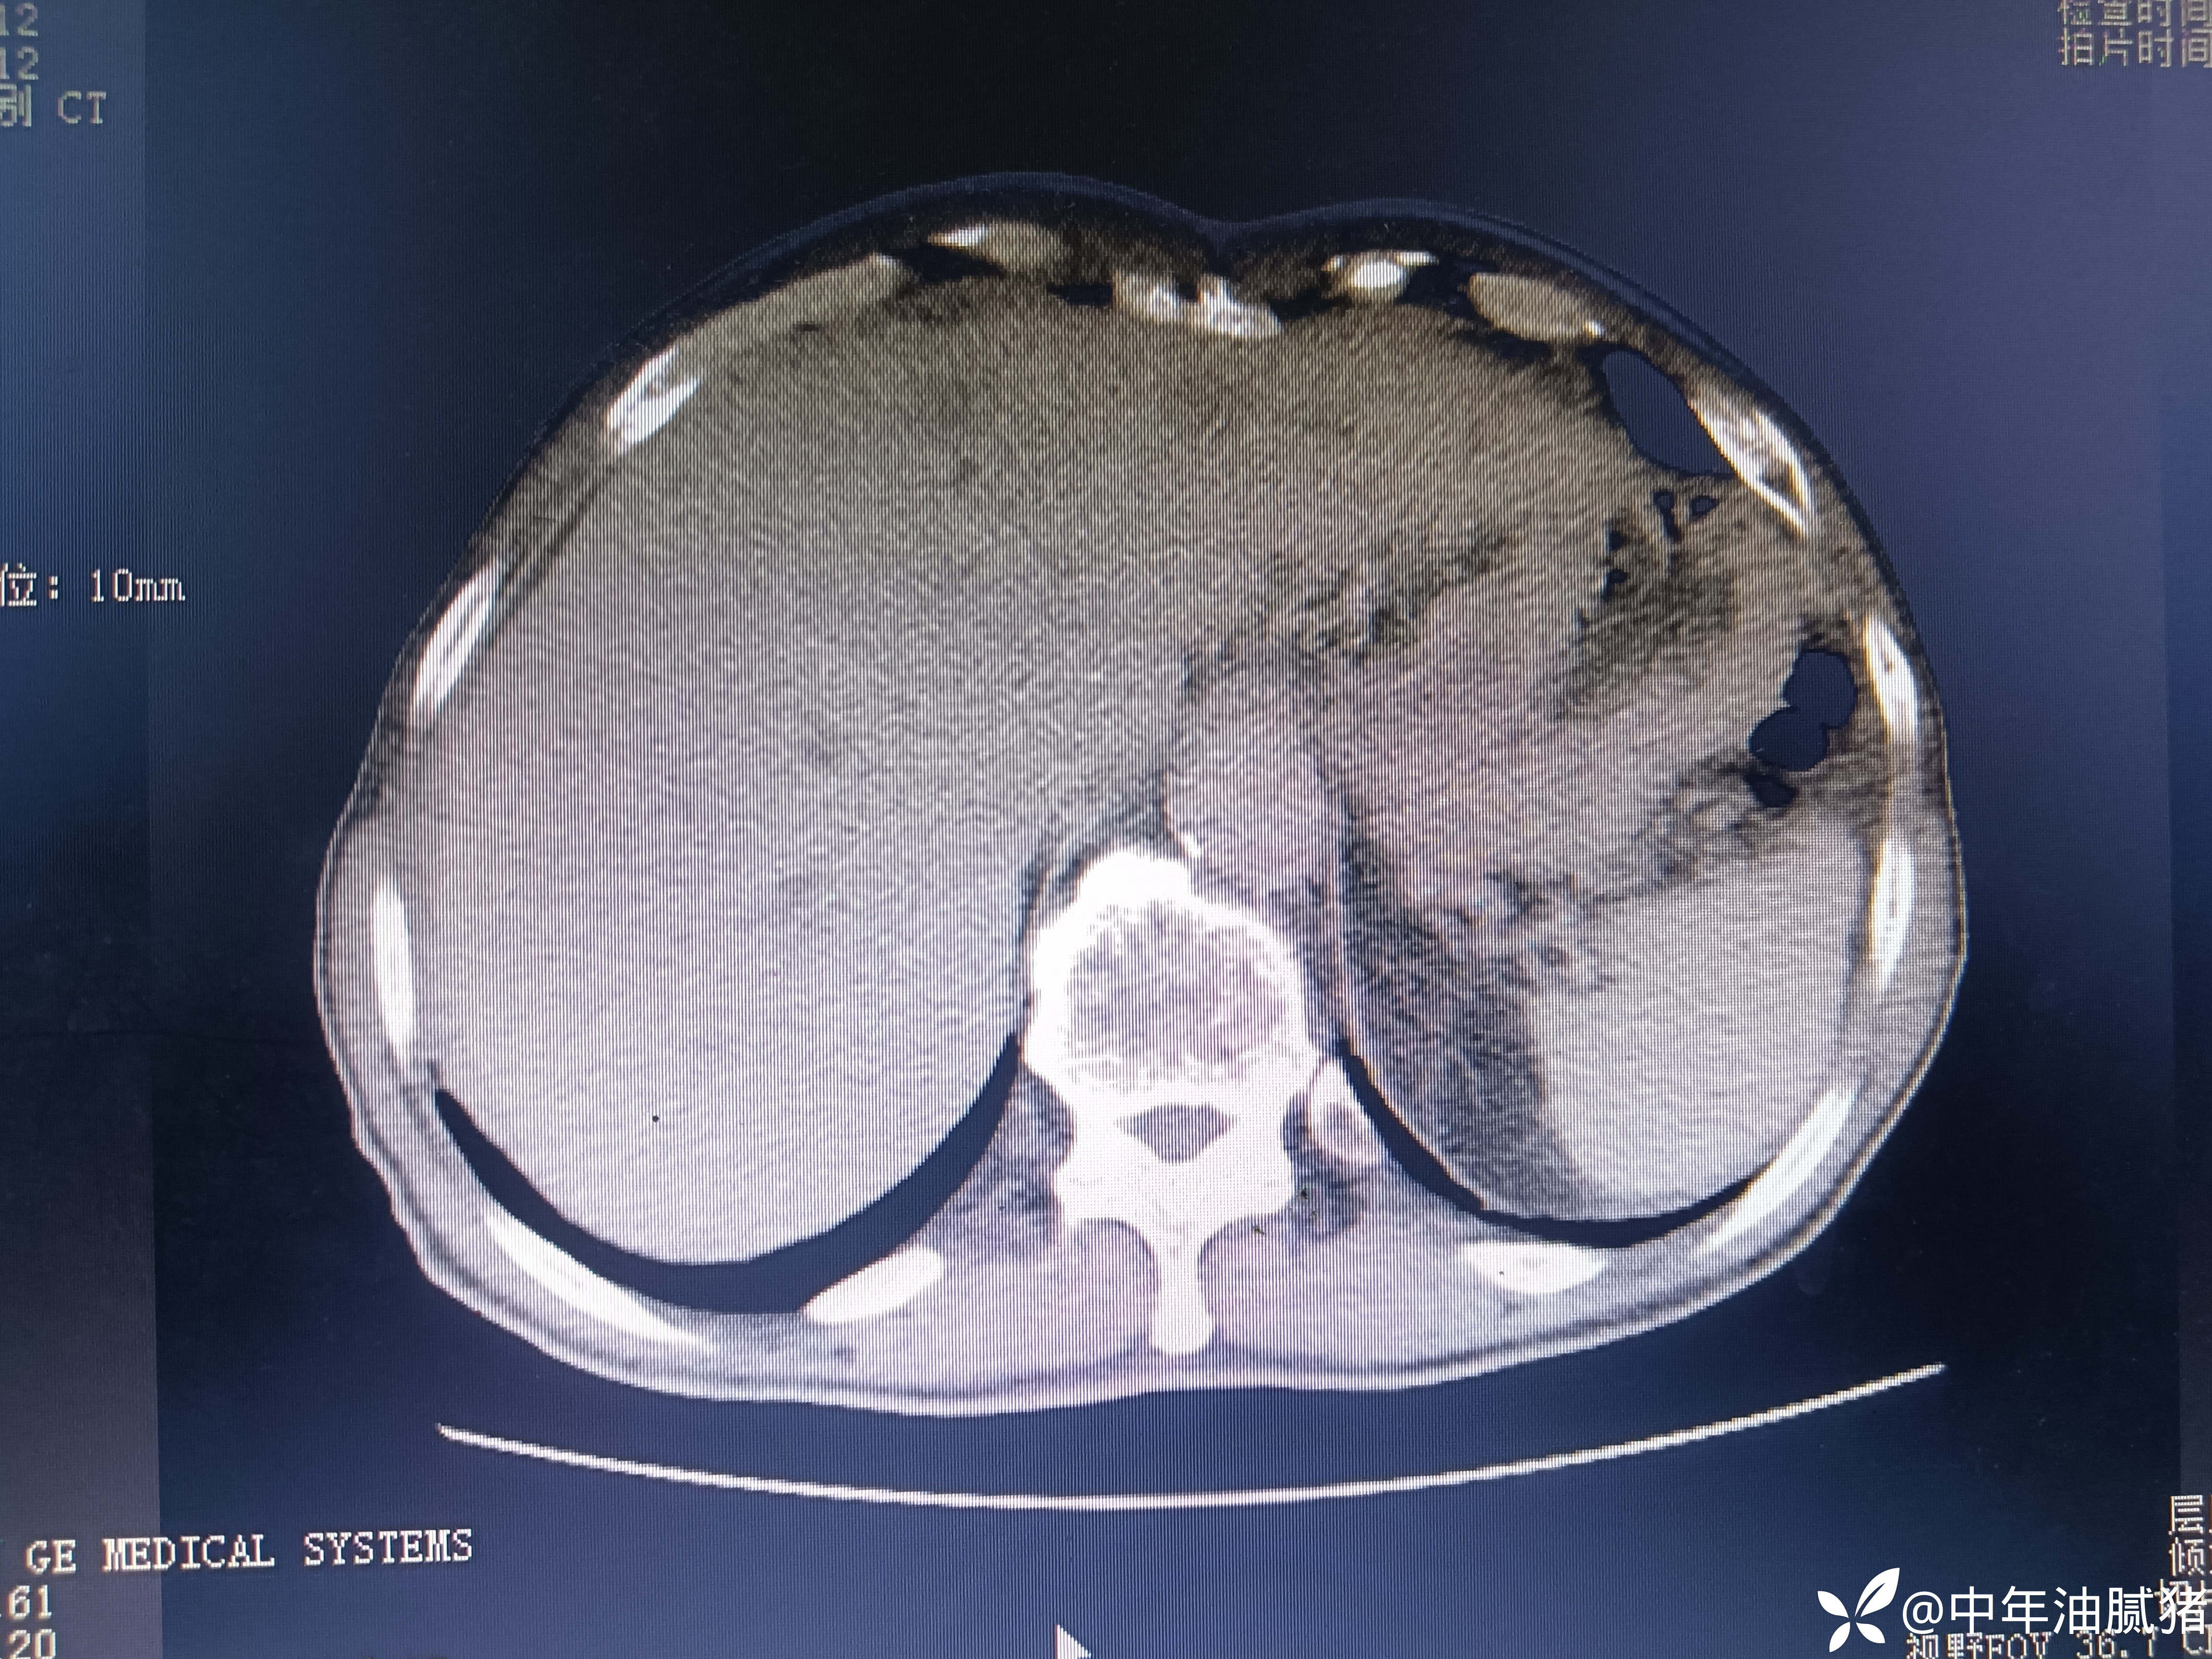

肺ct看到肝内病灶,行增强检查

建议增强ct.报告如下

考虑肝囊肿?让他走?

看后,我隐隐约约觉的不是肝囊肿那么简单?元芳,你怎么看?狄阁老,我也是这么认为!摇人,掏起手机:喂,w主任,请帮我看看这个ct。5分钟后报告修改如下